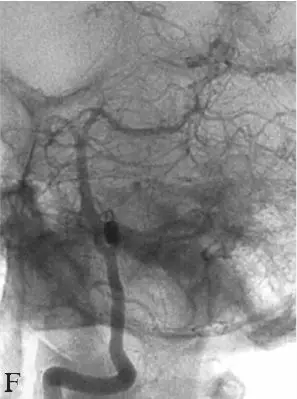

术后即刻无神经功能缺损。按蛛网膜下腔出血后常规处理,中性治疗,严密观察神经系统体征变化,2周复查全脑血管造影,提示动脉瘤无明显显影(图18-2E),来自长回旋动脉的代偿血流稳定(图18-2F)。出院时及1年后的临床随访mRS评分0分。

按蛛网膜下腔出血及动脉瘤单纯弹簧圈栓塞术后常规处理。患者术后恢复顺利,无神经功能缺损。出院时及术后7个月随访mRS 0分,术后7个月复查DSA提示动脉瘤完全不显影,基底动脉及双侧椎动脉血流通畅,显影未见异常(图18-4D~F)。